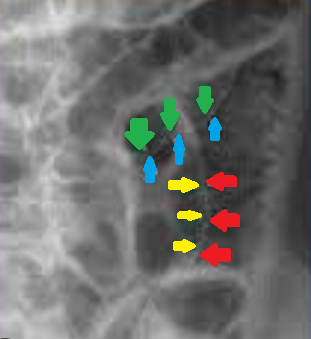

Πράσινο βέλος – εστιακή εξέλκωση κολικού βλεννογόνου. Κίτρινο βέλος – οίδημα και λεμφοκυτταρική διήθηση υποβλεννογόνιου χιτώνα (Ευγενική παραχώρηση Dr. V. Penopoulos)

Πράσινο βέλος – περιφλεβιδική λεμφοκυτταρική διήθηση σε υποβλεννογόνια θέση (Ευγενική παραχώρηση Dr. V. Penopoulos)